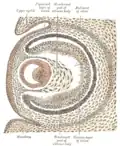

Optic cup and choroidal fissure seen from below, from a human embryo of about four weeks. -

Horizontal section through the eye of an eighteen days’ embryo rabbit. X 30. -